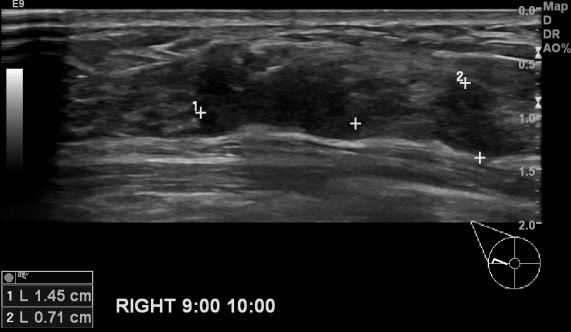

상기환자 건강검진상 이상소견으로 내원하신 40대 여성분으로 우측 9:00 ~10:00 시

방향에 의심스러운 멍울 조직검사 시행하여 우측 침윤성 유관암 진단 되었습니다.